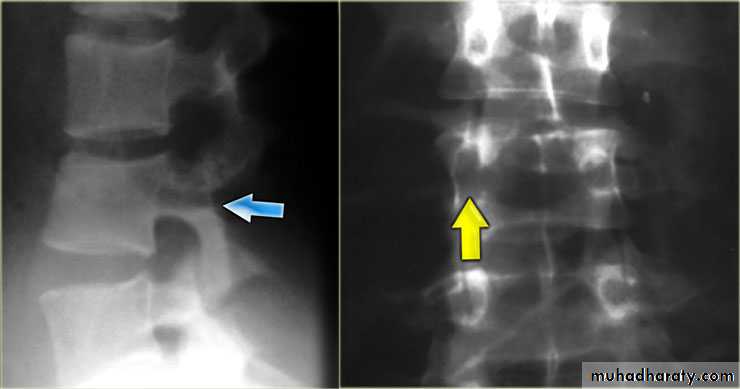

Wedge fracture

Burst fracture

Chance fracture

Fracture dislocation